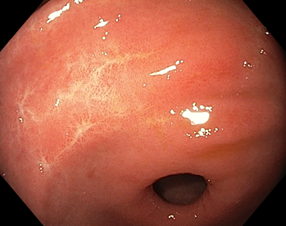

Рисунок 1. Стадии регрессии (заживления) язвы желудка и их характерные черты:

A (Active). Активная стадия (обострение)

A1. Слизистая оболочка, окружающая язву, выглядит набухшей в результате отёка, регенерация эпителия отсутствует.

A2. Отёк слизистой оболочки вокруг язвы уменьшился, край язвы отчётливо виден и в крае язвы появились первые ростки регенерирующего эпителия. По периметру язвы часто прослеживается красный ободок, а непосредственно по краю – циркулярный белый струп. Обычно, сходящиеся складки слизистой оболочки прослеживаются вплоть до края язвы.

H (Healing). Стадия заживления

H1. Слой белого фибрина, покрывающий язву, становится тонким, а регенерирующий эпителий распространяется непосредственно на основание язвы. Градиент между краем и дном язвы сглаживается. Но кратер язвы все еще очевиден, и край язвы отчётливо виден. Диаметр язвенного дефекта составляет примерно от половины до двух третей диаметра язвы в стадии A1.

H2. Язвенный дефект меньше, чем в стадии H1, и регенерирующий эпителий покрывает большую часть дна язвы. Площадь слоя белого фибрина составляет примерно от четверти до трети площади язвы в стадии А1.

S (Scarring). Стадия рубца

S1. Регенерирующий эпителий полностью покрывает дно язвы. Белый слой фибрина полностью исчез. Первоначально зона регенерации выглядит ярко красной. При прицельном осмотре можно увидеть большое количество капилляров. Сформировался "красный рубец".

S2. В срок от нескольких месяцев до нескольких лет исходно красный рубец принимает цвет окружающей слизистой оболочки. Сформировался «белый рубец».

Комментарий. Плановое эндоскопическое исследование подтверждает наличие язвенного дефекта, уточняет его локализацию, форму, размеры, глубину, состояние дна и краев язвы, позволяет выявить признаки пенетрации, рубцовой деформации и стенозирования просвета органа. Плановое эндоскопическое исследование дает возможность обнаружить другие сопутствующие изменения слизистой оболочки и определить нарушения гастродуоденальной моторики. Для оценки стадии язвенного процесса (обострение, заживление, рубцевание) целесообразно использовать общепринятую в мире классификацию Sakita-Miwa (рис.1).